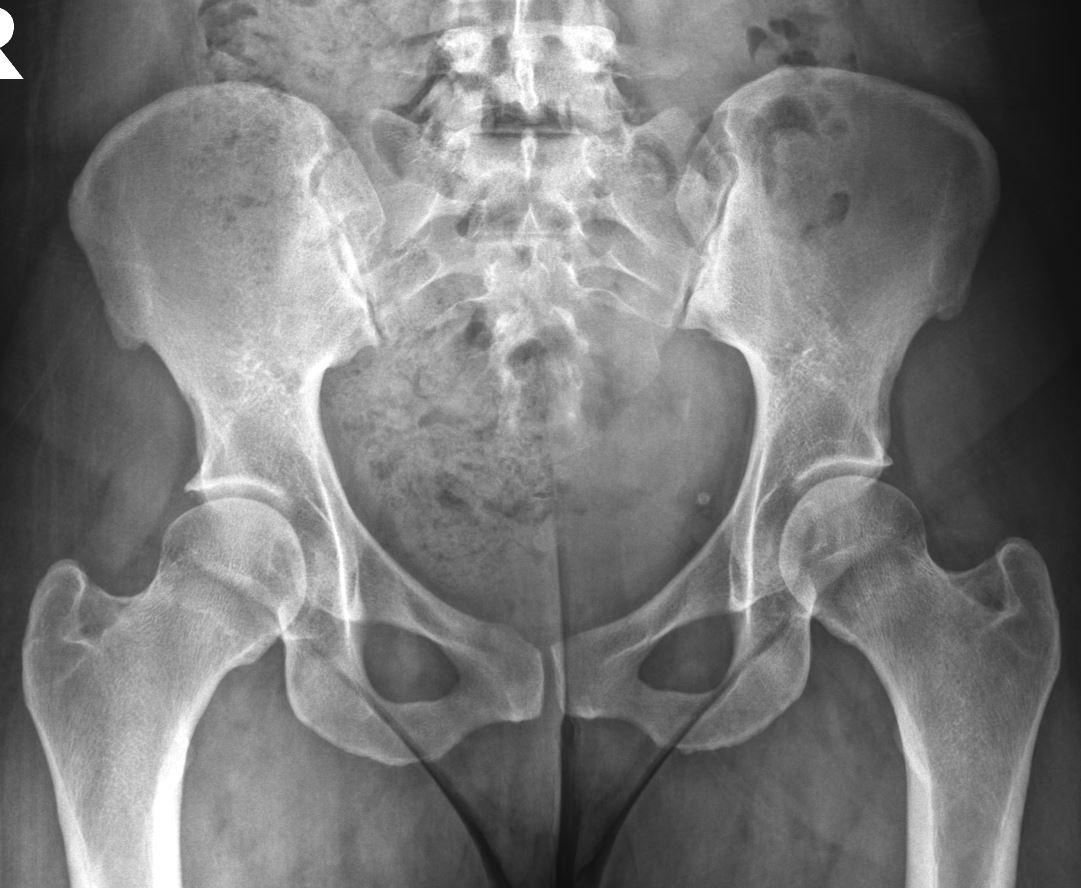

Seems symmetric, though this 30F complains only of 2 weeks Rt hip pain. I don’t think these would impinge on the labrum inferomedially…nobody is there.

I think there is also bilateral superior acetabular retroversion…maybe she has Pincer impingement?

It really seens she has a uncommom contour shape of the inferomedial femoral head-neck transition bilaterally.

Does she practices any sport? Although she doesn’t have any other imaging features, both ischiofemoral and femoroacetabular impingement symptoms can be due to suprafisiologic movements in sports, ie: impingement symptoms with no morfostrutural changes on imaging exams. I’ve seen it in runners and kick related sports (specifically football and muay thai).